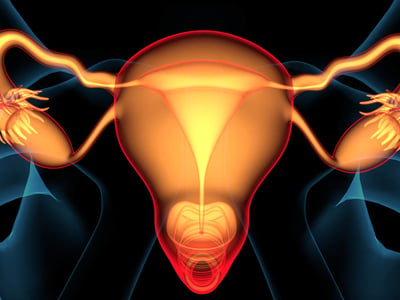

Jede Brust (Mamma) besteht aus 10 bis 20 Drüsenlappen mit jeweils zahlreichen Drüsen.

Die Brustdrüsen (Mammae) sind paarig angelegte Organe am Oberkörper jedes Menschen. Die Brustanlage ist bei Männern und Frauen gleich, über die Ausbildung der reifen Brust entscheidet lediglich der Einfluss von Östrogenen. Jede Brust besteht aus 10 bis 20 Lappen, die aus vielen Milchdrüsen zusammengesetzt sind. Die Ausgänge der Milchdrüsen münden in der Brustwarze (Mamille). Die Drüsenlappen sind eingebettet in Binde- und Fettgewebe. Dieses entscheidet auch über die individuelle Größe der Brust. Das Brustgewebe unterliegt hormonellen Einflüssen und verändert sich im Rahmen des Menstruationszyklus sowie in der Schwangerschaft.

- Die weibliche Brust besteht aus zahlreichen Drüsen, die in Drüsenlappen organisiert sind.

Die Brust besteht aus Drüsenlappen (Lobi glandulae mammariae), deren Drüsengänge zur Brustwarze führen. Die Drüsenlappen liegen eingebettet in Binde- und Fettgewebe (Interlobuläres Stroma). Die Brustwarze (Mamille)besteht aus einem Warzenvorhof (Areola mammae), dessen Farbe sich durch stärkere Pigmentierung von der umgebenden Haut abgrenzt .In der eigentlichen Mamille (Papilla mammaria) münden alle Ausführungsgänge der Milchdrüsen. Die Mamille hebt sich normalerweise leicht über das Hautniveau ab. Ist dies nicht der Fall und liegt die Brustwarze auf Hautniveau oder leicht eingesunken, kann das Stillen erschwert sein.

Die weibliche Brust besteht aus vielen Brustdrüsen, die in 10 bis 20 Lappen pro Seite angeordnet sind. Die Lappen sind eingebettet in Binde- und Fettgewebe.